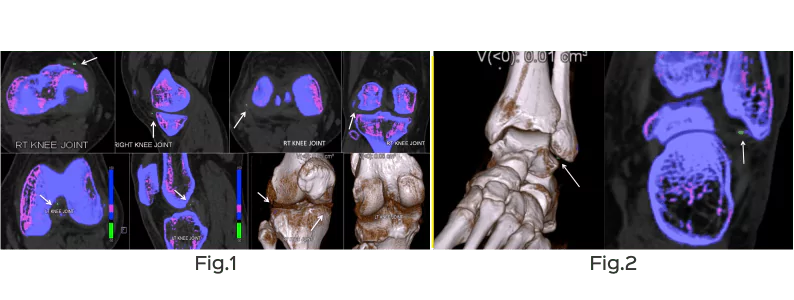

Keeping the dual energy ratio at 1.36, the uric acid crystals lie below the line and are differently color-coded (green), whereas the calcium deposits lie above the line. Hence diagnosis of gout can be easily made, non-invasively (Figs. 1, 2).

With DECT it is also possible to quantify the overall tophus burden or volume of urate deposition without any user variability. This makes it an ideal tool for evaluating even a small change in tophus burden and can be used for follow-up to document response to treatment.